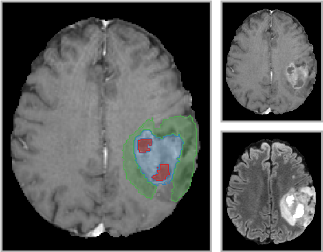

GBM tumor segmentation consists in delineating each region that composes a lesion: necrotic core (NC), enhancing tumor (ET), and vasogenic edema (ED). For that, it is necessary to use MRI sequences that reveal the multiple visual aspects of those regions. For example, FLAIR (T2 fluid-attenuated inversion recovery) activates the edema while T1Gd (post-contrast T1-weighted) activates the enhancing tumor and shows the necrotic core as a non-activated region [22, 6]. Some works show that additional T1 and T2 scans can improve the results, but not significantly compared to FLAIR and T1Gd only [14]. Figure 1 illustrates the different visual aspects of the regions of interest in the FLAIR and T1Gd scans, showing ED, ET, and NC on the left. On the right, it shows that ED can appear with parts saturated and parts with intermediate intensity values. Such differences in appearance may also occur for ET and NC in T1Gd images. Since the selected filter bank of the first layer should activate all relevant regions, the user intervenes by drawing markers in images with such differences and choosing filters from multiple executions of FLIM with different hyperparameters. Other appearance variations in shape, intensity, contrast, and size are presented in Figure 2.

|